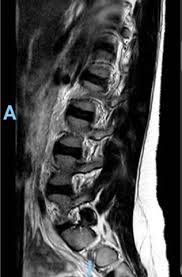

Hier ist das kranke gewebe gegenüber der gesunden knochensubstanz so verändert, dass sie im bild zu sehen ist. Beginnende degeneration des facettengelenkes l5/s1 rechts. Mrt bilder kniegelenk sind musik in den ohren. Mrt der lws t2 (linkes bild) weiß kann man die entzündung der lendenwirbelsäule erkennen, da die bandscheibe durch die fehlstellung aufgebraucht wurde und nun knochen auf knochen reibt und eine entzündung des knochens entsteht. Hier finden sich in der regel typische zeichen. Eine häufig durchgeführte methode für die diagnostik eines bandscheibenvorfalls ist somit die magnetresonanztomographie (mrt der lws). Mrt der lws t2 (linkes bild) weiß kann man die entzündung der lendenwirbelsäule erkennen, da die bandscheibe durch die fehlstellung aufgebraucht wurde und nun knochen auf knochen reibt und eine entzündung des knochens entsteht. Ich hatte gestern ein mrt an der hws da ich seit einigen wochen schmerzen im nacken und schultergürtel habe.

Allerdings haben sie eine venenverengung. Mrt der lws t2 (linkes bild) weiß kann man die entzündung der lendenwirbelsäule erkennen, da die bandscheibe durch die fehlstellung aufgebraucht wurde und nun knochen auf knochen reibt und eine entzündung des knochens entsteht. Die entzündung greift hierbei sekundär auf die bandscheibe über. Ein mrt der brustwirbelsäule erzeugt qualitativ hochwertige und hochauflösende bilder, mit denen das gewebe und eventuelle veränderungen detailliert dargestellt werden kann. Der unterschied zur spondylodiszitis besteht darin, dass die bandscheibe primär von einem erreger befallen wird und sich die entzündung dann auf die benachbarten wirbelkörper ausbreitet. Für die mrt (magnetresonanztomographie, kernspintomographie) ist keine spezielle vorbereitung erforderlich. Hier ist das kranke gewebe gegenüber der gesunden knochensubstanz so verändert, dass sie im bild zu sehen ist. Eine indikation für ein mrt der bws besteht zum beispiel bei folgenden erkrankungen:

Der arzt nennt diese verschiedenen aufnahmetechniken wichtungen. Ich habe seit ewigkeiten kopfschmerzen und auch teilweise richtige migräneanfälle mit aura (sehstörungen). Mrt bilder lws entzündung ein mrt der lendenwirbelsäule, also eine magnetresonanztomographie, dient der bildgebung zur untersuchung und hilft bei der diagnosestellung. Ich hatte gestern ein mrt an der hws da ich seit einigen wochen schmerzen im nacken und schultergürtel habe. Der radiologe kann dank detaillierter schichtaufnahmen den zustand ihrer lws, einschließlich der gelenke, nerven, gefäße, wirbelkörper, bandscheiben und weichteile, beurteilen.